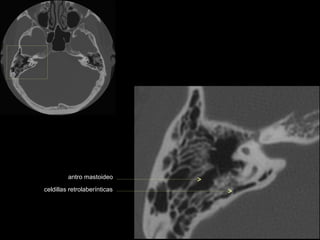

antro mastoideo

celdillas retrolaberínticas